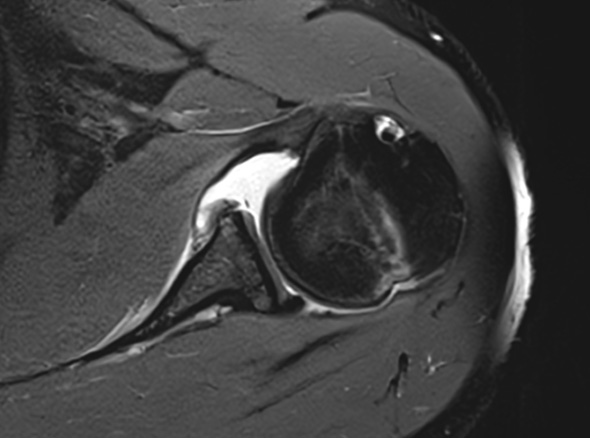

어깨는 운동범위가 가장 넓은 만큼 끊임없이 수축하고 긴장하게 됩니다.

이 때문에 안정을 유지하기 쉽지 않아 불안정함을 유발합니다.

젊은 층에서 외상으로 인해 발생하게 되면 재발이 많이 됩니다.